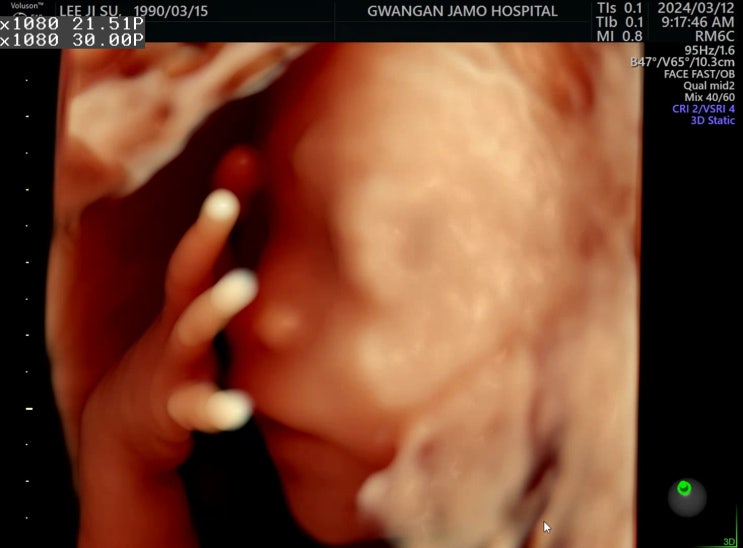

26w0d? 4D입체초음파, 임신성당뇨검사 날!

약국에서 철분제 구매 바우처 사용O 26w0d? 디데이가 두숫자로 줄어들음 4D입체초음파랑 공포의임당검...